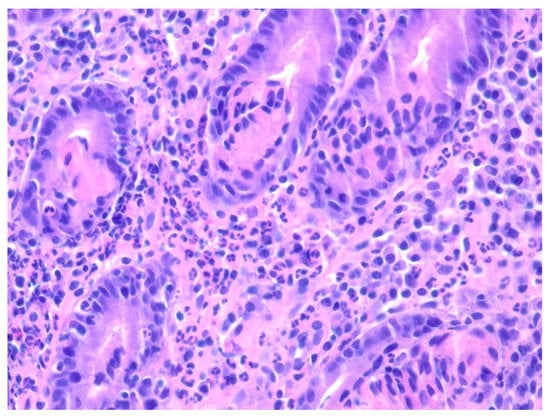

| 1 | F | 66 | Skin | Fundus, cardia, and body | Polypoid lesions with superficial ulcers | Esophagus, duodenum, mediastinum, cervical soft tissue, pancreas | Metastatic malignant melanoma | Radiotherapy and immunotherapy | Comfort care and death 5 days after EGD diagnosis of metastasis |

| 2 | M | 84 | Lymphoid | Fundus and cardia | Ulcerated and necrotic mass | Liver, urinary bladder | Diffuse large B-cell lymphoma | None | Death in 2 months after EGD diagnosis of metastasis |

| 3 | F | 35 | Lung | Fundus | Fungating mass | Esophagus, mediastinum | Large-cell neuroendocrine carcinoma | Chemotherapy-carboplatin/ etoposide | Death 1 month after EGD diagnosis of metastasis |

| 4 | F | 73 | Kidney | Fundus and body | Multiple large friable masses | Liver and lungs | Clear cell renal carcinoma | Nephrectomy, chemotherapy, immunotherapy (Axitinib) | Death 10 days after EGD diagnosis of metastasis |

| 5 | M | 76 | Lung | Body | Cratered ulcers | Liver, bone and adrenals | Small cell carcinoma (poorly differentiated neuroendocrine Ca) | None | Death 7 days after EGD diagnosis of metastasis |

| 6 | M | 61 | Lymphoid | Unknown | Clean based ulcer | None | Marginal zone lymphoma | Rituximab, Zanubrutinib, umbrasilib. OCHOP regimen currently | Progressive disease per latest scans despite therapy |